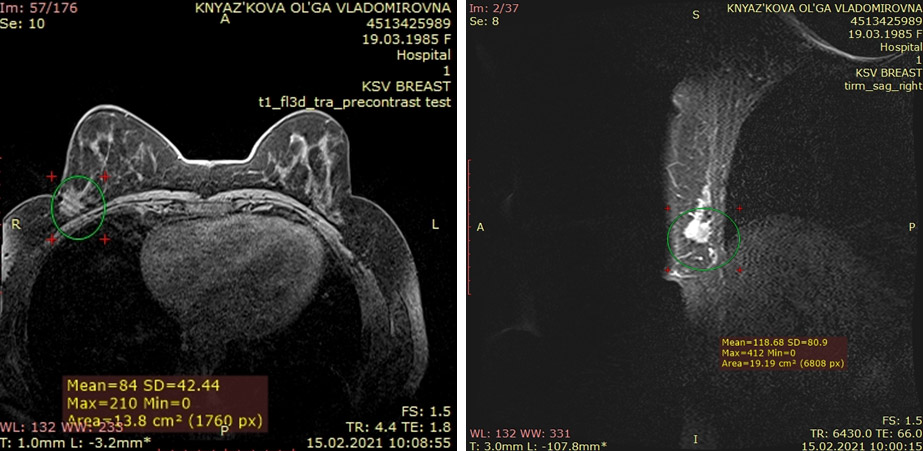

Пациентка О.В. 1985 г.р.

Диагноз: люминальный B, HER2 отрицательный тип, рак правой молочной железы T2N0M0 G2. 4 курса неоадьювантной химиотерапии по схеме AC. Стабилизация.

Операция: радикальная секторальная резекция правой молочной железы с подмышечной лимфадиссекцией.